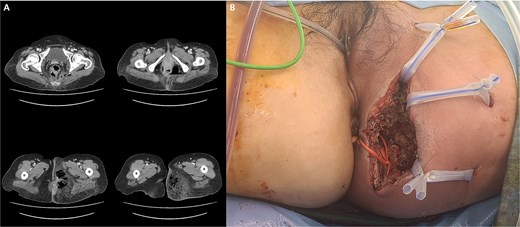

A 59-year-old female patient was referred to our hospital with severe left buttock pain lasting 5 days. Although she had no co-morbidities, she was previously diagnosed with hemorrhoids at the local clinic due to perianal pain persisting for 1 month. The patient had no medical or surgical history. Her initial body temperature was 38.4°C, blood pressure was 110/60 mmHg, heart rate was 98 beats/min, and her oxygen saturation was 98% on room air. On physical examination, erythema and hardness were noted in the left perineum and buttock areas. Additionally, dilated piles were observed on anus (Fig. 1). Given the clinical suspicion of FG, a computed tomography (CT) scan and blood tests were urgently performed. The CT scan demonstrated abscess formation along with severe emphysema in the left perineum and buttock (Fig. 2A). Blood tests showed leukocytosis of 41 840/μl with neutrophil left shift and an elevated C-reactive protein level of 33.4 ng/dl. The patient was finally diagnosed with FG, indicated by a severity index score of 6 points [6]. After initiating fluid resuscitation and broad-spectrum antibiotics, extensive debridement of the perineum was executed (Fig. 2B). However, due to clinical deterioration after general anesthesia, staged debridement was performed, and the patient was admitted to the intensive care unit for stabilization. Subsequent debridement and a diverting colostomy were performed 3 days after surgery. After 1 week in intensive care, the patient was transferred to the general ward where additional wound debridement and revisions were conducted. Two months after initial surgery, the surgical wound had completely healed, and wound closure was performed. Although inflammation had subsided, indurated tissue persisted around the anus, which had become so constricted that a digital rectal examination was impeded. Therefore, a biopsy of the perianal tissue was taken. Histopathological examination identified moderately differentiated squamous cell carcinoma, and HPV 16 was detected (Fig. 3). Pelvic magnetic resonance imaging (MRI) revealed anorectal cancer with invasion into both levator muscles and indeterminate lymph nodes in the bilateral external iliac, right obturator, and bilateral inguinal chains (Fig. 4). Positron emission tomography demonstrated an intensely hypermetabolic mass extending from the anus to the rectum, accompanied by multiple hypermetabolic lymph nodes in the left common iliac, left external iliac, right internal iliac, and bilateral inguinal regions (Fig. 5). Consequently, concurrent chemoradiotherapy (CCRT) employing mitomycin and 5-fluorouracil was initiated. The patient received a total radiation dose of 63 Gy in 35 fractions over 8 weeks. Elective nodal irradiation included the bilateral inguinal, internal iliac, and mesorectal nodal basins, in accordance with standard guidelines. Although follow-up MRI after CCRT showed a significant reduction in the size of the primary tumor and lymph nodes, we decided to perform a radical resection (Fig. 6). Robotic abdominoperineal resection was performed 3 months after CCRT, during which lateral pelvic lymph node dissection wasn’t conducted, as post CCRT imaging showed indeterminate lymph nodes suggestive of remission. Histopathological examination of the specimen revealed no residual tumor (ypT0N0). Although a minor surgical site infection occurred at the perineal wound, it was successfully treated with oral antibiotics and dressings at an outpatient setting. At 10 months post-surgery, the patient reported left pelvic pain, and follow-up imaging revealed suspected metastases in the left psoas, para-aortic area, supraclavicular node, right 10th rib, and lung. Consequently, the patient was scheduled for palliative chemotherapy.

(A) Abscess formation with emphysema in the left perineum and buttock on abdominal pelvic CT scan. (B) Postoperative images after incision and drainage.